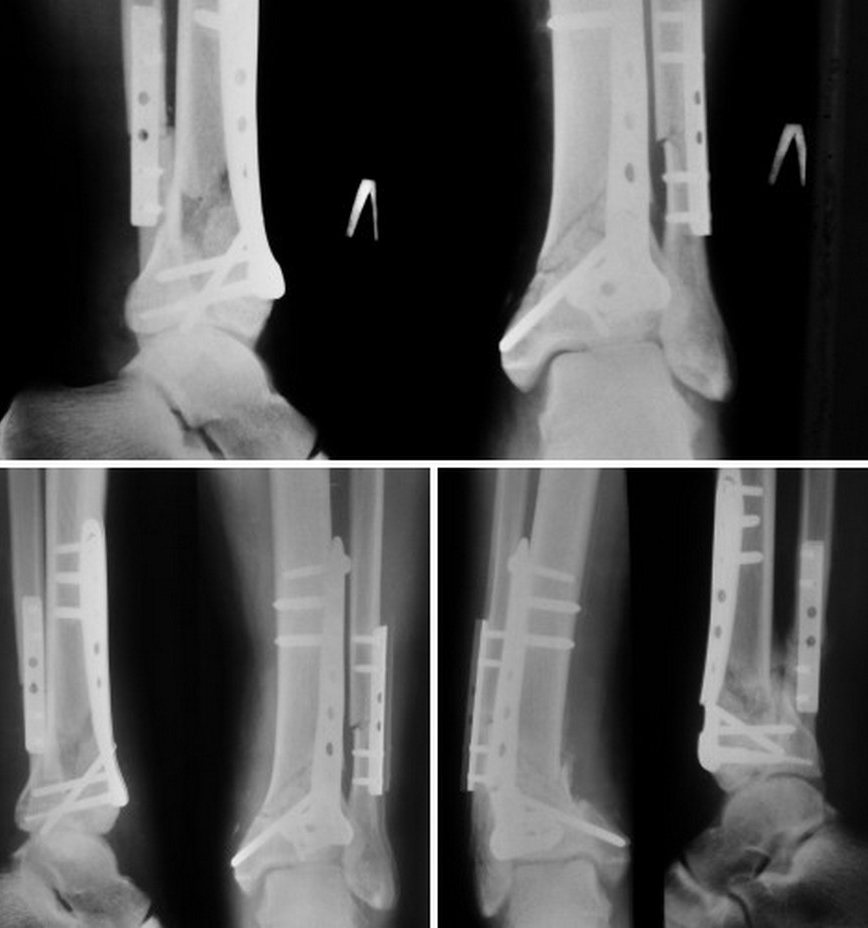

Верхний снимок - контроль после операции

Нижний левый - контроль 8 недель

нижний правый - после перелома пластины

Пластита не причем. Слишком ранняя полная нагрузка. Стоит сделать то же самое .

Однозначно ЧКДО ,после удаления конструкций,с коррекцией наступившей деформации.

Собственно, результат, кому интересно.

Операции: Удаление пластины, ЧКДО АВФ с одномоментным устранением смещения пилона и умеренной дистракцией.